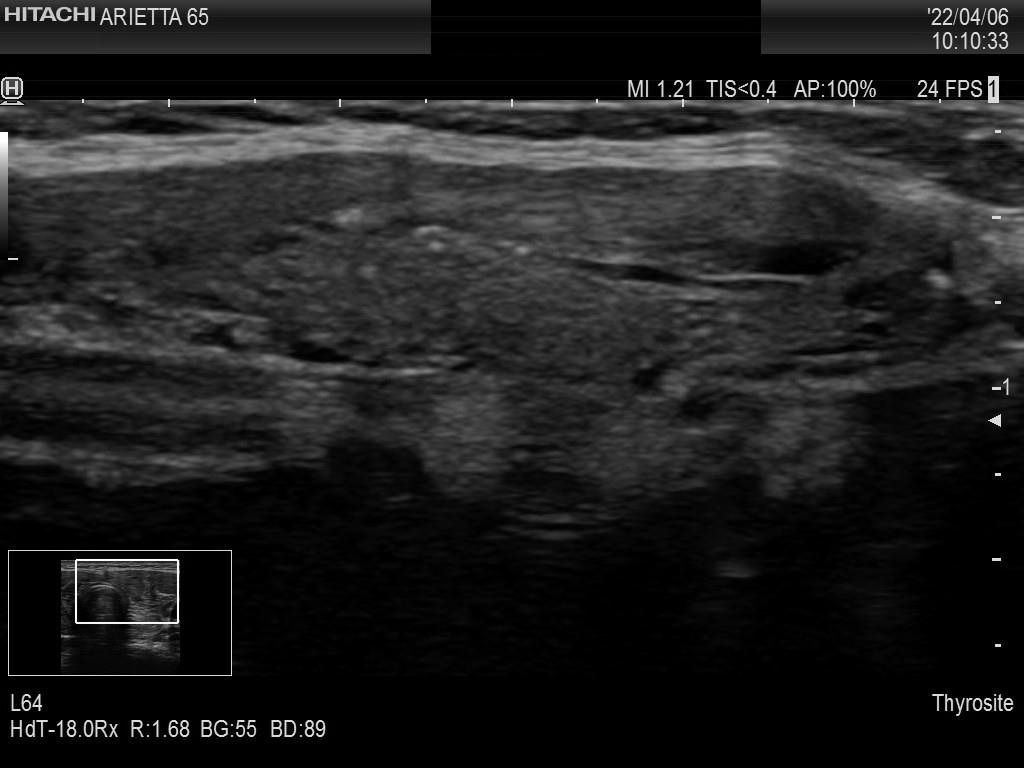

Intranodular hyperechogenic figures - case 694 (ultrasonographic picture 12)

Left lobe, longitudinal scan, enlargement. These echogenic granules would be difficult to judge if we would not aware of the presence of comet-tail artifacts.